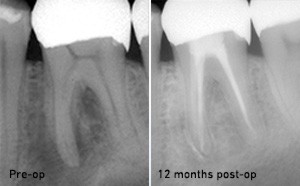

Endodontie

D'excellents résultats de traitement peuvent être atteints car FONALaser tue les germes très efficacement, stimule la croissance des tissus et des os et accélère la guérison.